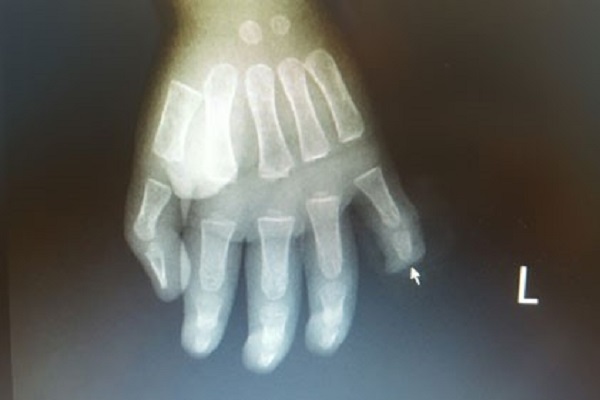

Bố mẹ lơ là, trẻ 17 tháng tuổi đứt rời đốt ngón tay do nghịch dao

- Các bác sĩ bệnh viện Việt Nam Thụy Điển Uông Bí (Quảng Ninh) vừa phẫu thuật cho một bệnh nhi 17 tuổi đứt lìa đốt trên của ngón tay út sau khi nghịch dao.

- Bệnh viện Trường Đại học Y khoa Vinh vừa phẫu thuật thành công cho một bệnh nhân 27 tuổi bị đạn bắn vỡ cổ tay, vết thương sưng nề, bầm tím do nhập viện muộn.